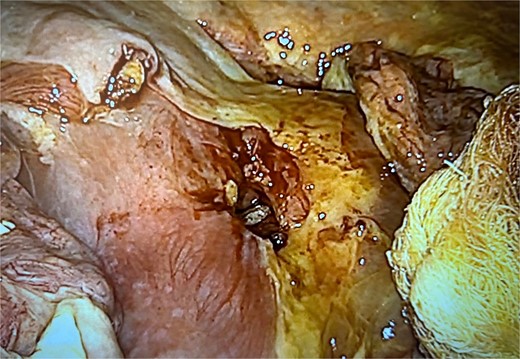

Exploratory laparoscopy revealed a large amount of intestinal fluid, fibrinous exudates, edematous intestinal loops, and a 1-cm MU at the level of the gastrojejunal anastomosis (Fig. 1). The margins were debrided and the defect was closed with absorbable poliglecaprone using a continuous suture technique. The closure was reinforced by an omental patch (Figs 2 and 3). The abdominal cavity was aspirated and irrigated. She was discharged from the hospital without complications. An endoscopy 6 months postoperatively revealed a persistent MU (Fig. 4).